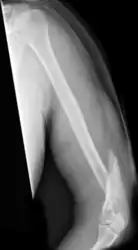

A transverse fracture of the humerus shaft

A spiral fracture of the distal one-third of the humerus shaft